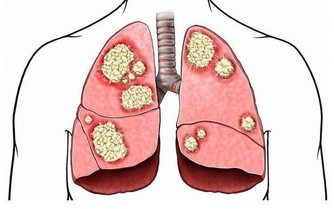

5、預防感冒,適時增衣

秋冬交替季節晝夜溫差較大,疾病多發,患者應特別注意,積極預防感冒等疾病。

由於糖尿病患者的免疫力較低,容易感冒,

而感冒對人體而言是應激因素,會刺激體內的應激激素升高,從而引起血糖的升高;

感冒若處理不當可引起糖尿病酮症。

因此,糖尿病患者一定要根據氣候變化增減衣服,預防感冒。

因寒冷可刺激體內升糖激素增多,使血糖升高加重糖尿病病情,

而且寒冷可引起血管收縮,使血流減慢,易誘發心腦血管疾病,

所以糖尿病患者要多注意,防“秋凍” 。